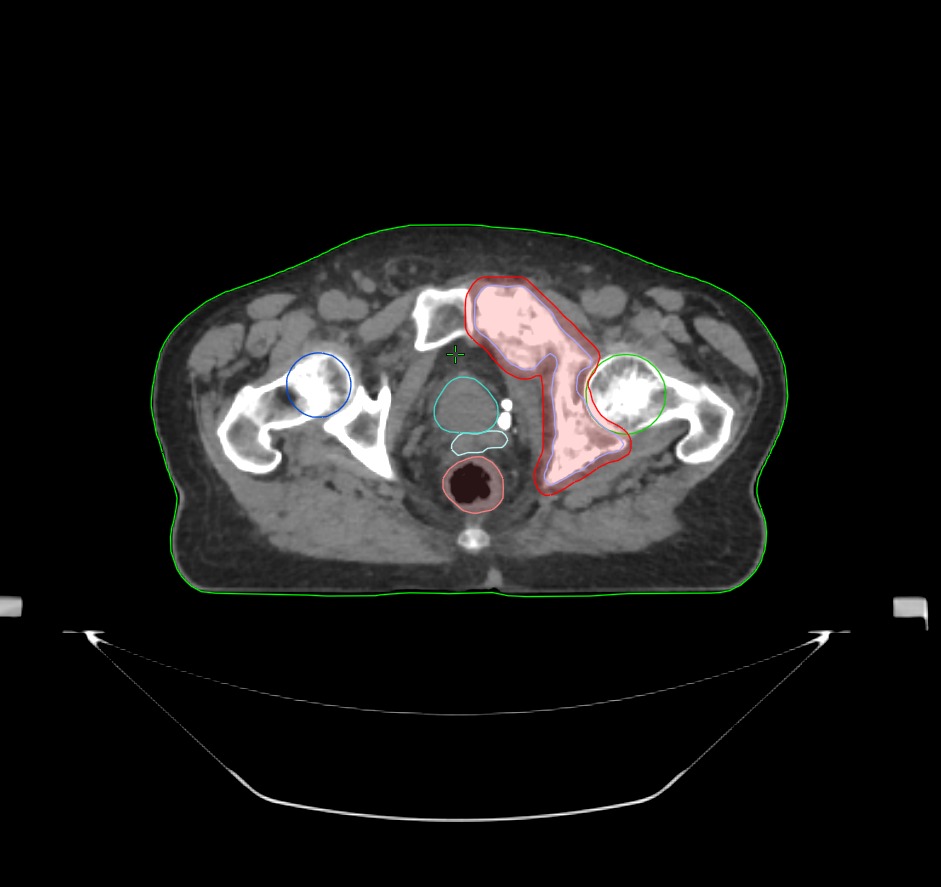

Особенность работы в дневном стационаре радиотерапевтическом № 2 — возможность применения методики стереотаксической лучевой терапии (СТЛТ/SBRT/SRS) на линейном ускорителе Varian Truebeam. Уникальность аппарата обусловлена особенностями его конфигурации: размером лепестков коллиматора. Они позволяют точно формировать пучок излучения, повышать точность за счет подведения максимальных доз излучения к опухолевым очагам, минимально затрагивая при этом здоровые ткани. Такой подход значительно повышает эффективность лечения и снижает риск осложнений.